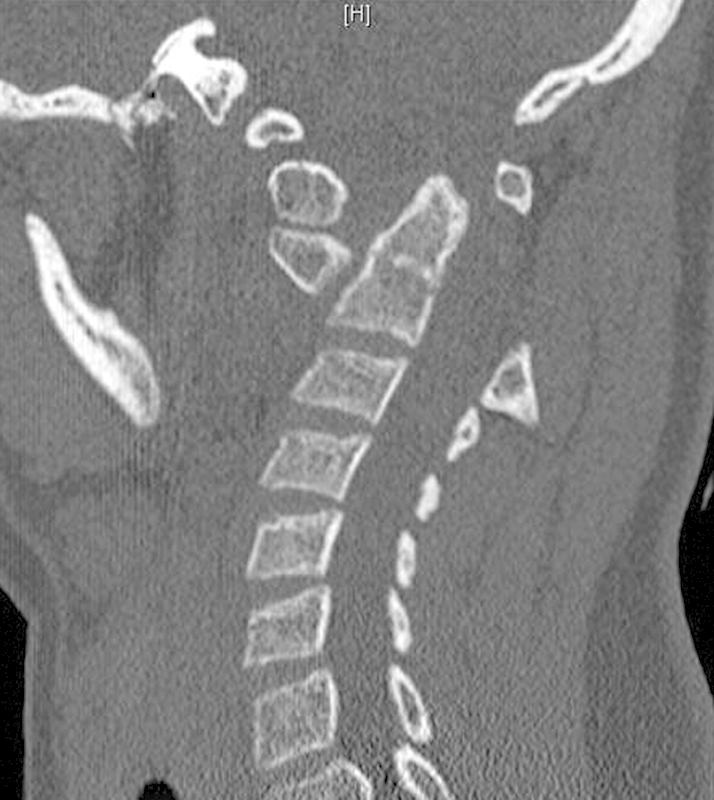

Study Design Retrospective case review. Objective Atlantoaxial instability with and without basilar invagination poses a considerable challenge in management regarding reduction, surgical approach, decompression, instrumentation choice, and extent of fusion. A variety of strategies have been described to reduce and stabilize cranial settling with basilar invagination. Modern instrumentation options included extension to the occiput, C1-C2 transarticular fixation, and C1 lateral mass-C2 pars among others. Since not all cases of cranial settling are the same, their treatment strategies also differ. Factors such as local vascular anatomy, amount of subluxation, need for distraction, and shape of occipital condyles will dictate level and type of instrumentation. The objective of this study was to outline treatment options and provide a rationale for the surgical plan. Methods Two cases of C1-C2 instability in patients with Down syndrome are described. Case 2 underwent C1-C2 instrumented fusion, whereas case 1 involved posterior instrumented fusion to the occiput. Results Both patients tolerated the procedures well. There were no complications. Minimum follow-up was 1 year. There was no loss of reduction. Solid arthrodesis was achieved in both cases. Conclusion Successful reduction can be achieved with both C1-C2 instrumented fusion as well as O-C instrument fusion. Factors such as local vascular anatomy, amount of subluxation, need for distraction, and shape of occipital condyles will dictate level and type of instrumentation.